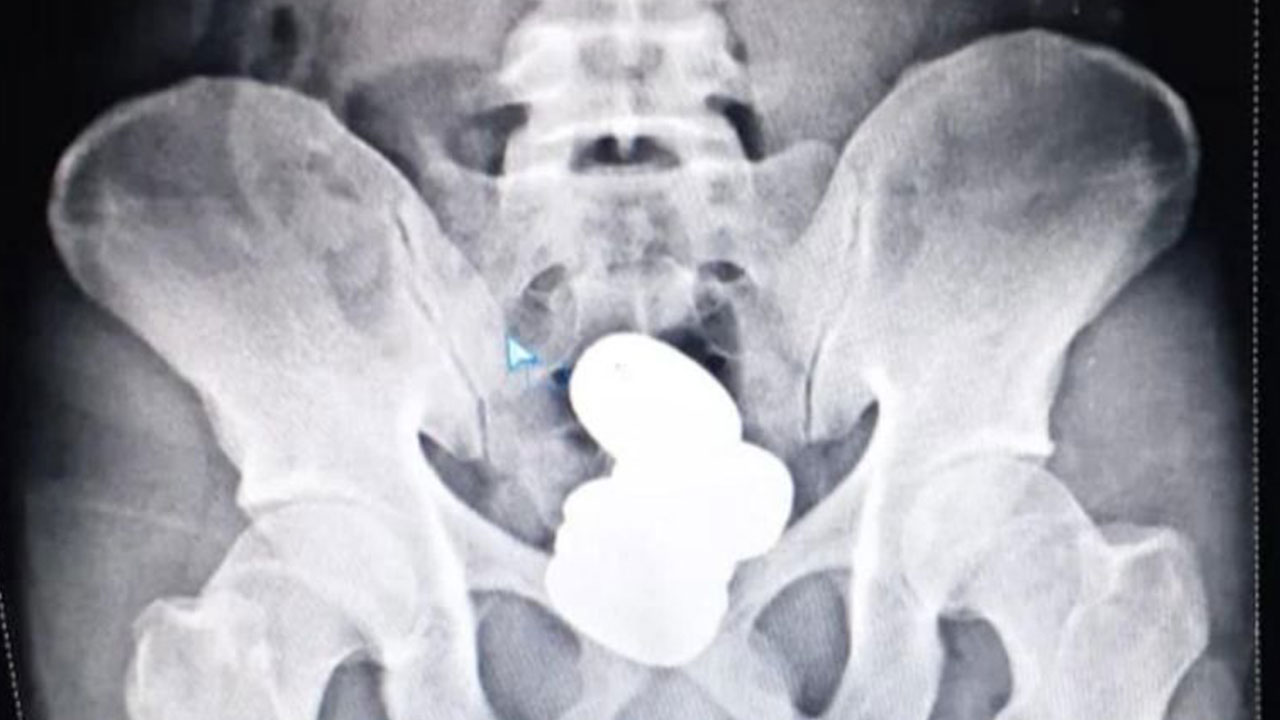

Las autoridades le hicieron una radiografía que reveló la presencia de cuatro cápsulas en el recto que contenían en total más de 900 gramos de pasta de oro, por un valor aproximado de 56 mil 664 dólares, según el comunicado de las fuerzas de seguridad.